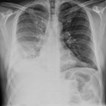

Over the course of a week, patients receiving both drugs saw a 30 per cent reduction in fluid volume seen in their chest X-rays, compared to 17 per cent for the placebo group. There was no effect above placebo for either drug on its own.

‘We've shown that the therapy clearly improves drainage of fluid in patients with pleural infection,' says Dr Rahman of Oxford University. ‘But we still need to be cautious - it is not yet certain whether clearance of the chest X-ray translates in to important outcomes for patients, like reduced surgery rates, fewer fevers, and shorter stays in hospital. Although our results strongly suggest this is the case, larger studies are now needed to confirm this."